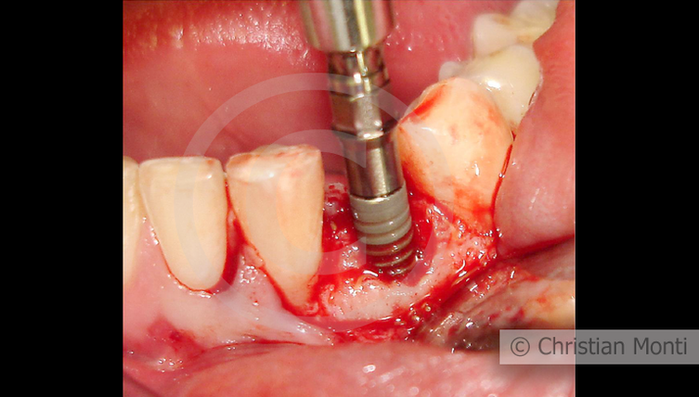

EDENTULIA SINGOLA

Impianto in sostituzione di un canino deciduo